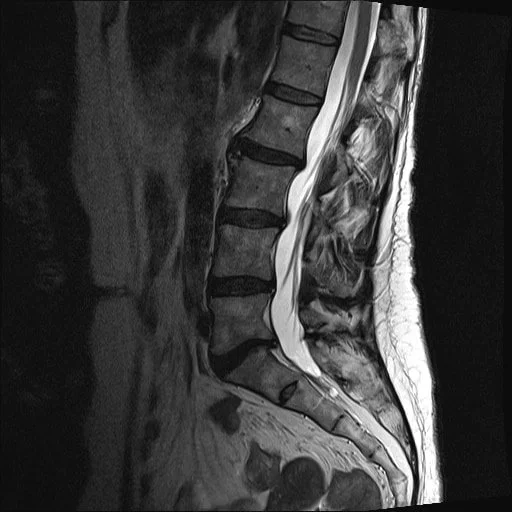

MRI scan of a person's lower spine showing vertebrae, discs, and spinal canal.

This is a sagittal (side-on) T2 MRI image of a normal lumbar spine in a young adult. As a T2 scan shows water (and fat) as bright, the CSF (spinal fluid) is white as is the nucleus of the disc. The discs themselves show normal height and no bulging meaning that there is minimal degeneration.